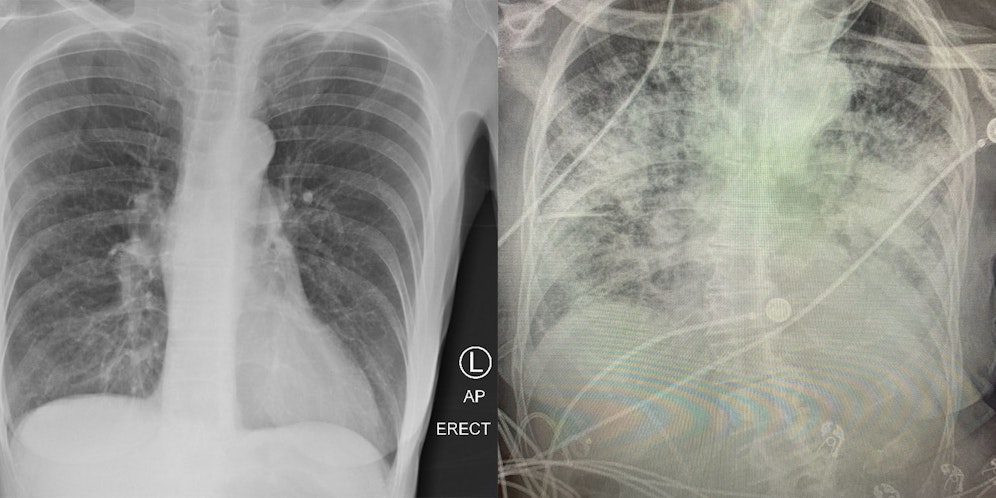

Die Spätfolgen des Coronavirus auf den menschlichen Körper sind noch nicht umfassend erforscht, erste Berichte von Medizinern geben aber Grund zur Sorge. Eine Assistenzprofessorin in Texas, Brittany Bankhead-Kendall, schlägt jetzt Alarm: “Nach einer überstandenen Covid-Erkrankung sehen Lungen schlimmer aus als jede Raucherlunge, die wir je gesehen haben”, so die Ärztin auf Twitter. Wie der Fernsehsender WGN America berichtete, zeigen Röntgenbilder einen dramatischen Unterschied zwischen einer gesunden Lunge, einer Raucherlunge und einer “Post-Covid-Lunge”.

Luft wird auf den Bildern schwarz dargestellt, Knochen und organisches Material weiß. Laut Bankhead-Kendall können Röntgen von Covid-Patienten fast vollständig weiß aussehen, was auf intensive Vernarbung und einen Mangel an Sauerstoff hinweist. Im Vergleich dazu zeigen Raucherlungen auch nach jahrelangem Tabakkonsum noch weniger ausgeprägte Spuren.